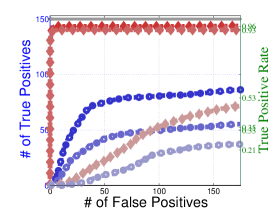

We investigate changing for differentially present edges by setting in a separate simulation (Figure 5) for the banded and hub-type graphs for Case II type differential edges. For this simulation, we use population correlations rather than covariances in order to eliminate variations in scale across subjects. Additionally for fair comparisons here, we limit the number of differential edges to 25 per group and fix the degree of the common support to be .

Lastly, in Figure 5, we study the effect of letting the network structure vary across subjects by decreasing the differential group edge probability, . Our method continues to perform well for . However, when the differential edge probability drops further to , we see that both and the standard approach have greatly reduced statistical power, as one would expect. Despite this, continues to outperform the standard approach.